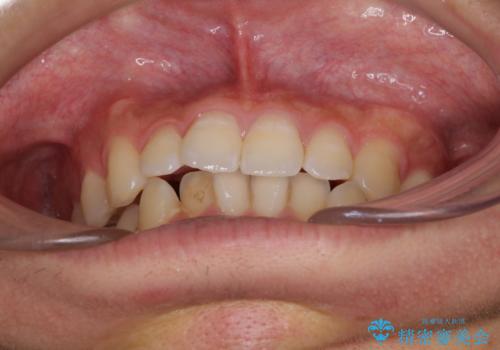

- 口元の突出感を治したいとのことで来院された患者様です。

抜歯をして口元を下げなければならないほど出っ歯ではなかったため、少しずつ治療ゴールを変更しながら仕上げていきました。

気になっていた前歯の飛び出した印象は、最終的にはスッキリと引っ込み、大変満足していただきました。